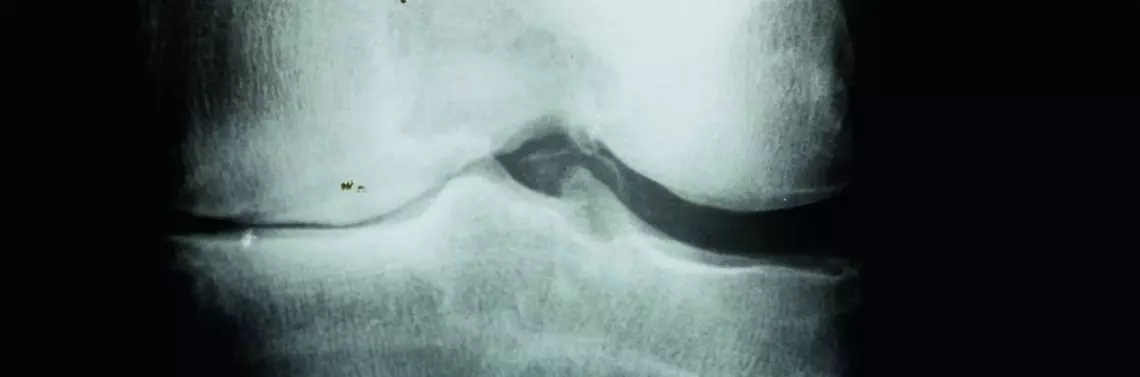

Definicja choroby zwyrodnieniowej zaproponowana przez ekspertów z American Academy of Orthopaedic Surgeons, National Institute of Arthritis and Musculoskeletal and Skin Diseases, National Institute on Aging, Arthritis Foundation i Orthopaedic Research and Education Foundation mówi o tym, że schorzenie to jest wynikiem działania różnych czynników zarówno mechanicznych, jak i biologicznych prowadzących do destabilizacji procesów odbudowy i degradacji chrząstki stawowej oraz podchrzęstnej warstwy kości i dotyczy wszystkich tkanek stawu. Choroba prowadzi do rozmiękania, włókienkowatości, owrzodzeń i ubytku chrząstki stawowej, a także stwardnienia i zagęszczenia podchrzęstnej tkanki kostnej oraz powstawania osteofitów i torbielek podchrzęstnych.